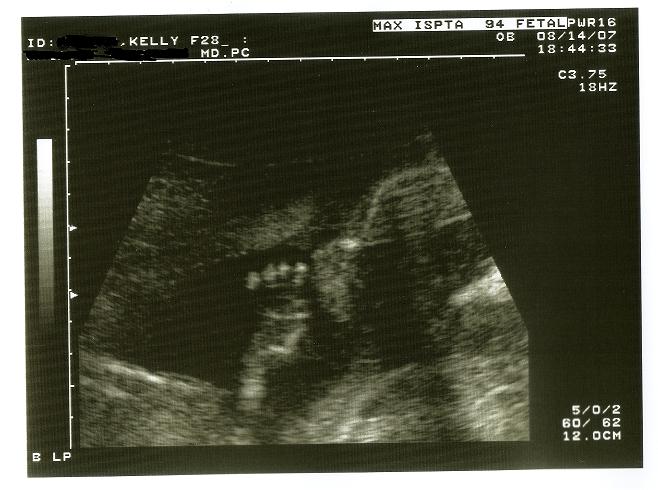

My 22 week sono was my favorite, I could see DS sucking his thumb. and we could see his ribs and all his fingers and toes.

Sorry you didnt have a good experience Image Attachment(s):